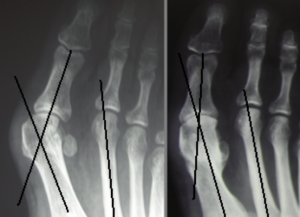

Una radiografia che fa vedere il prima e il dopo